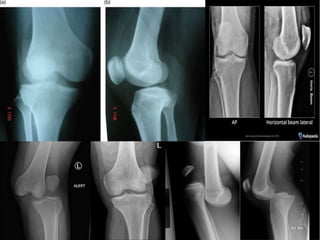

• Plain radiographs;

• AP and lateral

• Forty-five–degree oblique and/or plateau views if an associated fracture is

suspected